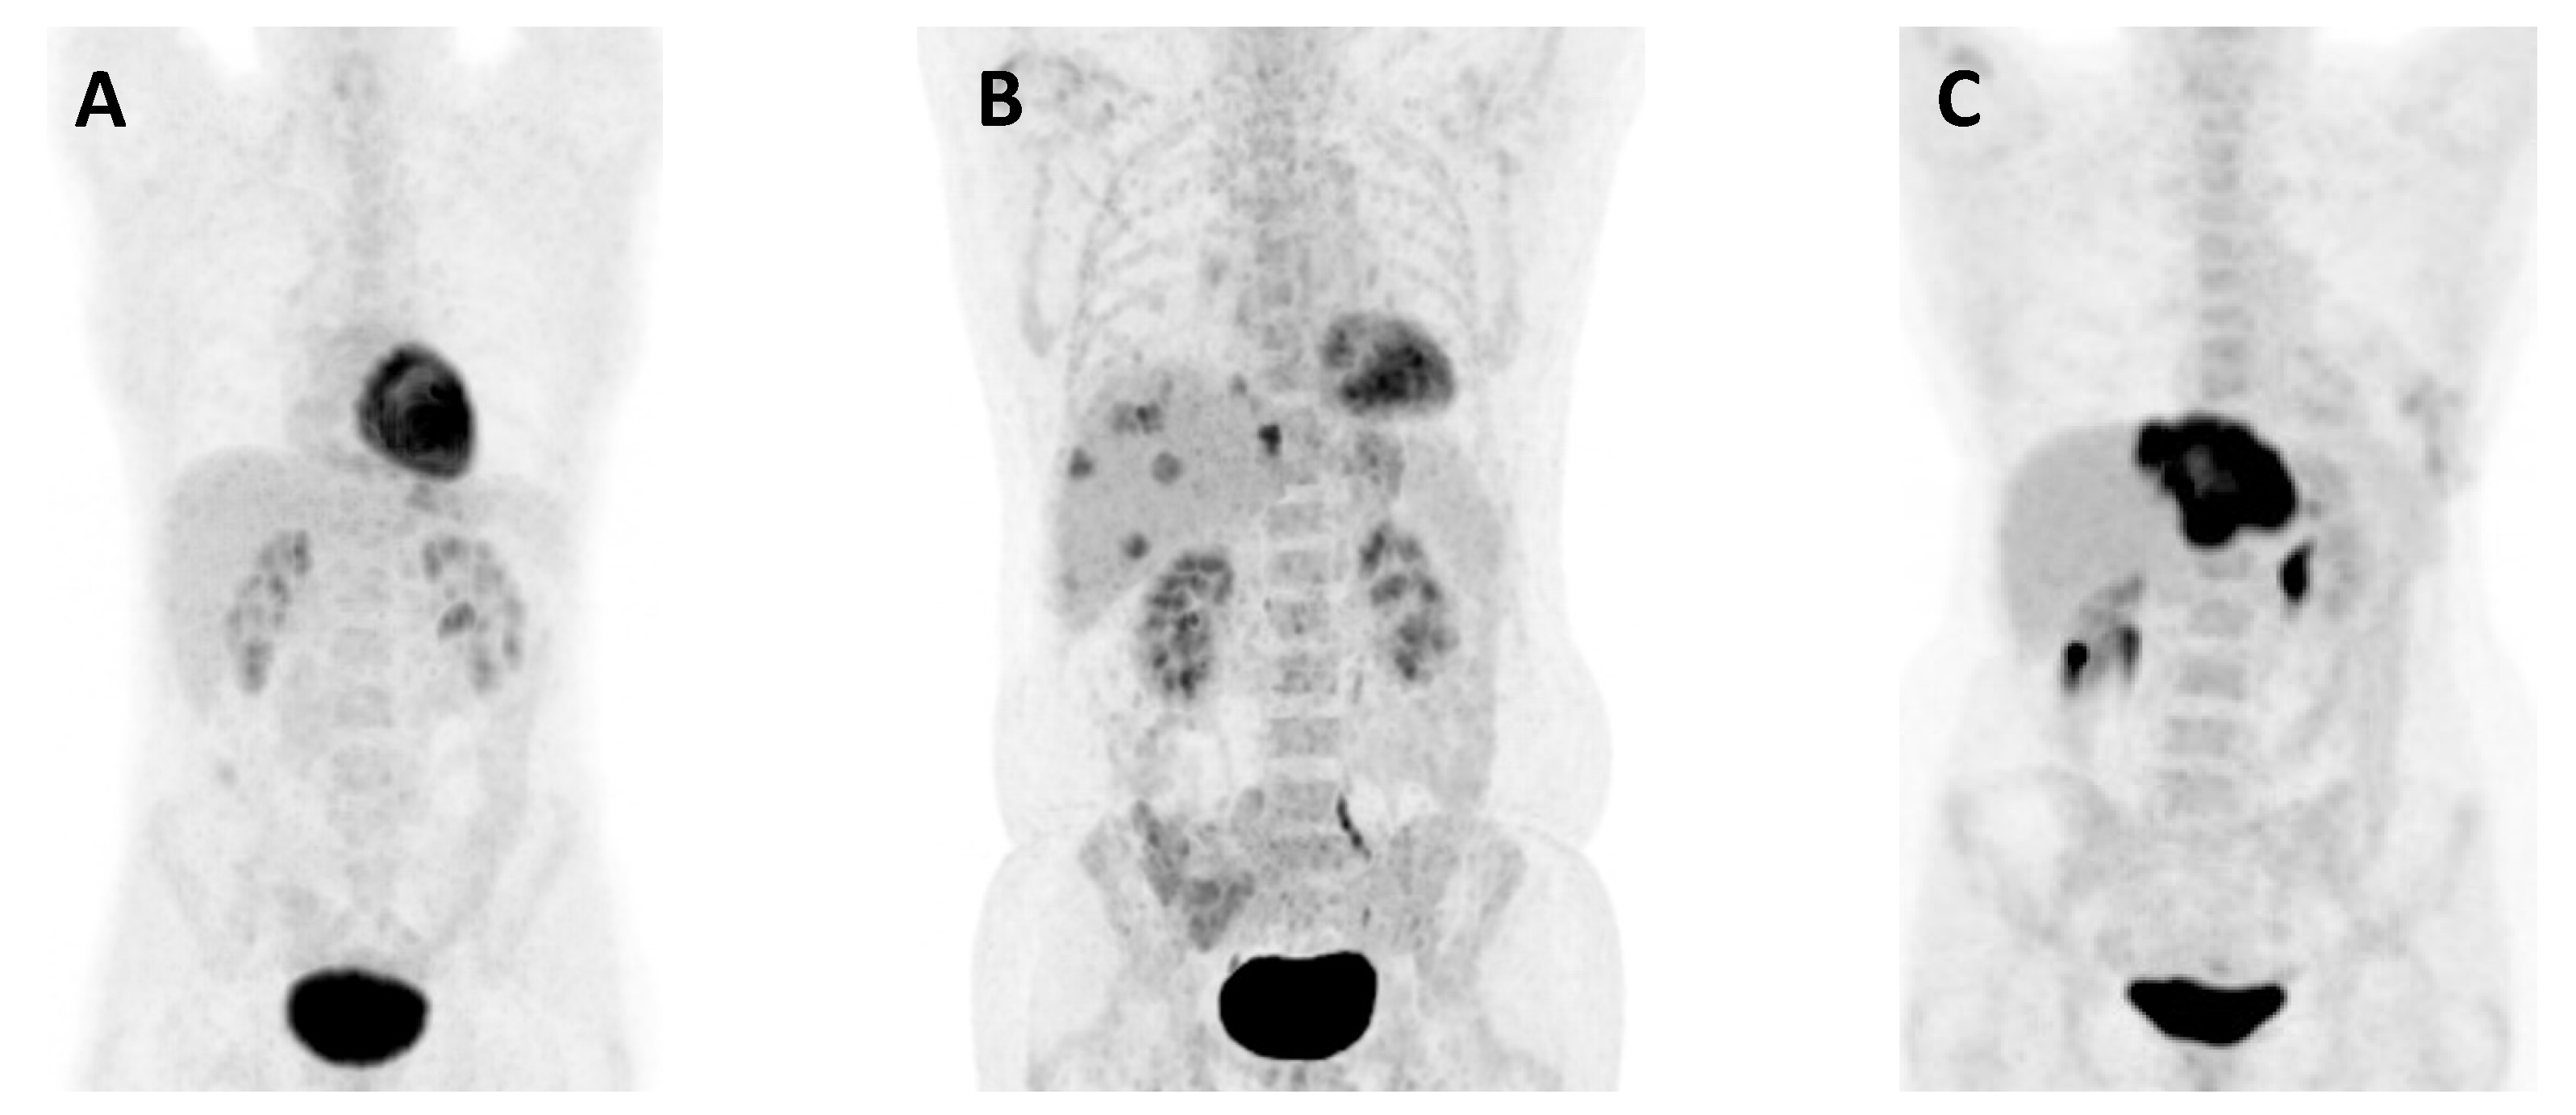

- Grut, H.; Revheim, M.E.; Line, P.D.; Dueland, S. Importance of 18F-FDG PET/CT to select patients with nonresectable colorectal liver metastases for liver transplantation. Nucl. Med. Commun. 2018, 39, 621–627. [Google Scholar] [CrossRef]